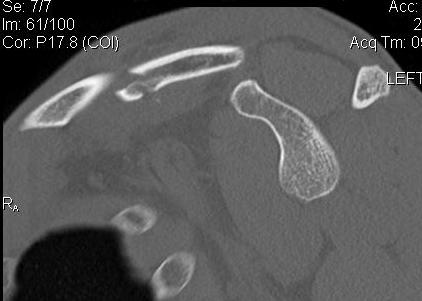

Scapular neck fracture with clavicle fracture